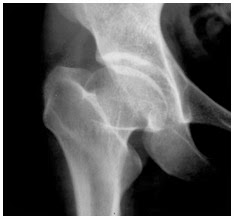

La tête de son fémur et sa hanche était atteinte.Les cellules osseuses mourraient et modifiait la forme de la tête fémorale.

est une nécrose (forme de dégat cellulaire avec mort prématurée et non programmée des cellules dans le tissu vivant.) ischémique (avec diminution de l'apport de sang dans l'organe) de la tête fémorale en croissance.Pour garder ses propriétés mécaniques, un os doit être irrigué par du sang.

La nécrose ischémique signifie que l'os meurt du fait de l'absence d'irrigation sanguine. Il est important de noter que cette maladie survient chez un sujet qui grandit car la nécrose de la tête du fémur qui survient chez l'adulte n'évolue pas du tout de la même manière.

Les radiographies du bassin de face et des hanches de profil montrent des anomalies de la tête du fémur. Il faut pourtant savoir que pendant les deux premiers mois d'évolution de la maladie les radiographies peuvent être normales.

Dans le livre "Raggi di luce" (Les rayons de lumière) du journaliste et auteur italien Paolo Brosio, les docteurs montrent les radiographies de la guérison de l'os, le montrant déjà cassé et les os manquants et après sa guérison.